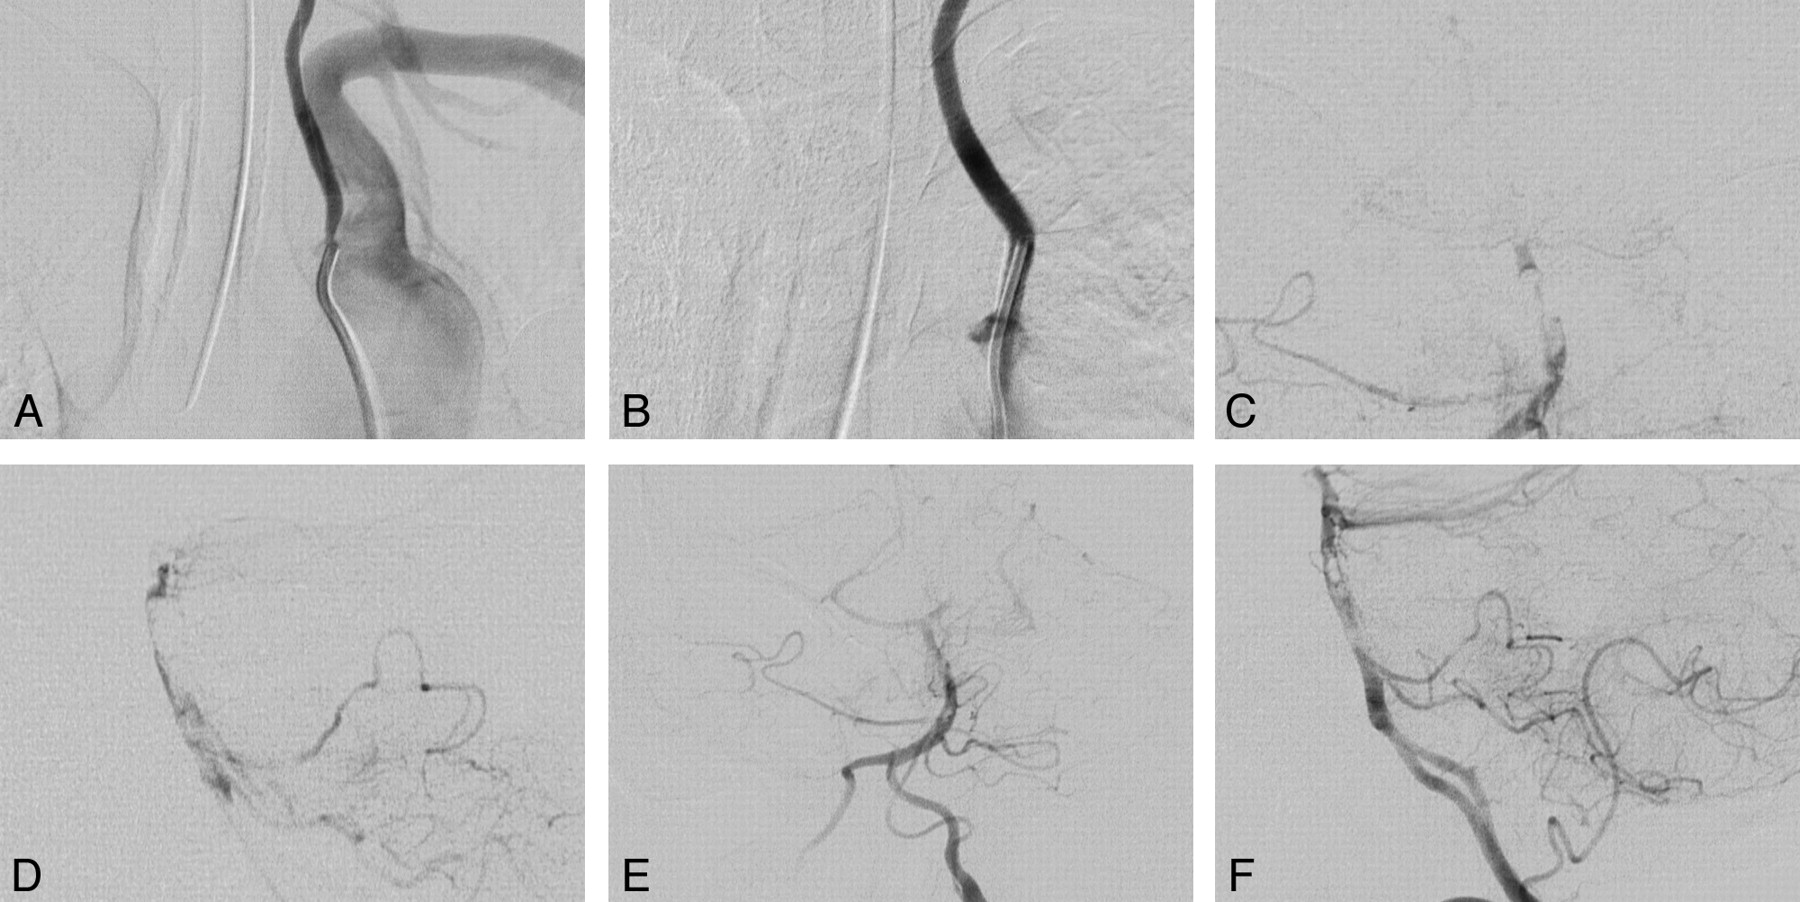

A 50-year-old man who presented with right medullary syndrome, followed by right hemiparesis, slurred speech, and diplopia 6 days later.

A, Left vertebral angiogram, anteroposterior view, showing a high-grade stenosis of the left vertebral artery origin from the aortic arch.

B, Left vertebral angiogram after placement of an ACS multilink Tristar coronary stent (3 mm in diameter x 30 mm length).

Anteroposterior (C) and lateral (D) views of selective basilar angiogram, showing multiple clots and distal basilar occlusion.

Anteroposterior (E) and lateral (F) views of left vertebral angiogram, showing reperfusion of the posterior circulation after infusion of 14 mg of tPA.